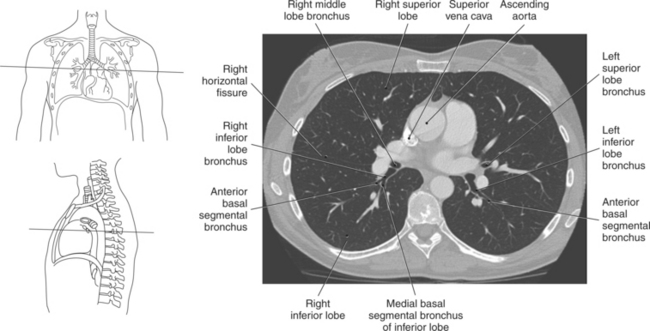

The lungs are the organs of respiration, where gaseous exchange occurs between the respiratory air and blood. They are composed of a spongelike material, the parenchyma, and surrounded by a layer of serous membrane. The large conical-shaped lungs extend up to or slightly above the level of the first rib at their apex and down to the dome of the diaphragm at their wide concave-shaped bases or diaphragmatic surfaces (Figure 6.9). Each lung has a mediastinal or medial surface that is apposed to the mediastinum, and a costal surface that is apposed to the inner surface of the rib cage. Each lung also has an inferior, anterior, and posterior border. The inferior border extends into the costodiaphragmatic recess of the pleural cavity, and the anterior border of each lung extends into the costomediastinal recess of the pleural cavity (Figure 6.10). Two prominent angles can be identified at the medial and lateral edges of the lung bases. The medial angle is termed the cardiophrenic sulcus, and the lateral angle is termed the costophrenic sulcus (Figure 6.11 and 6.12). The lungs are divided into lobes by fissures that are lined by pleura and may extend as far as the hilum (Figure 6.13). The right lung has three lobes (superior [upper], middle, and inferior [lower]), whereas the left lung has just superior (upper) and inferior (lower) lobes (Figures 6.6 and 6.11 through 6.13). The inferior lobe of the right lung is separated from the middle and superior lobes by the oblique fissure, termed oblique because of its posterosuperior to anteroinferior course. Separating the middle lobe from the superior lobe is the horizontal fissure (Figures 6.9 and 6.14, A). An oblique fissure also separates the superior and inferior lobes of the left lung (Figure 6.11). The left lung has a large notch on the medial surface of its superior lobe called the cardiac notch and a tonguelike projection off its inferoanterior surface termed the lingula. Each lung has an opening on the medial surface termed the hilum (Figures 6.14 through 6.16). This opening acts as a passage for mainstem bronchi, blood vessels, lymph vessels, and nerves to enter or leave the lung and is commonly referred to as the root of the lung.

The trachea bifurcates into the left and right mainstem (primary) bronchi at approximately the level of T5. This location is commonly referred to as the carina (Figure 6.9). The right main bronchus is wider, shorter, and more vertical in orientation then the left. At the hilum the mainstem bronchi enter the lung and divide into secondary or lobar bronchi. Secondary bronchi correspond to the lobes of the lungs, thus with three divisions on the right (superior, middle, inferior) and two divisions on the left (superior and inferior) (Figure 6.9, and 6.18 through 6.20). There is further division of the secondary bronchi into tertiary or segmental bronchi that extend into each segment of the lobes (bronchopulmonary segments) (Figure 6.21 and Table 6.1). There are typically 10 segments within each lung. Each bronchopulmonary segment is functionally independent and can be individually removed surgically. The bronchial tree continues to divide many times into smaller bronchi, then into bronchioles (Figure 6.22). Each bronchiole continues to divide until it reaches the terminal end as alveoli, which are the functional units of the respiratory system. Gaseous exchange between alveolar air and capillary blood occurs through the wall of the alveoli.